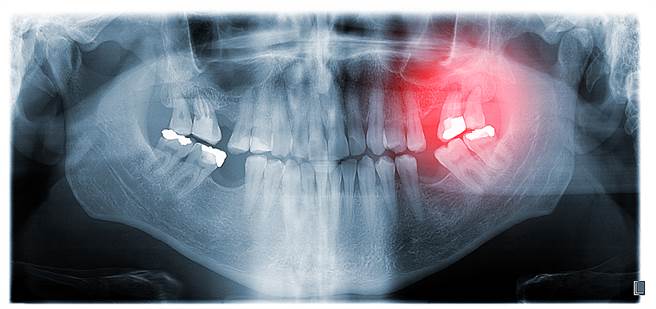

结果发现,在长达22至28年的追踪中,共出现199例食道癌与238例胃癌。拥有牙周病史的参与者,罹患食道癌的风险增加43%,罹患胃癌的风险则增加52%;相较于没有缺牙的参与者,缺牙2颗以上的参与者罹患食道癌的风险提升43%,罹患胃癌的风险则上升33%。

此外,与无牙周病史与无缺牙的参与者相比,罹患牙周病者不论其无缺牙、缺一颗以上牙齿,罹患食道癌的风险都增加59%;罹患牙周病不缺牙者,得到胃癌的风险增加50%,而掉1颗以上牙齿者罹患胃癌风险增加68%。

由于引起牙周病的福赛斯坦纳菌(tannerella forsythia)与牙龈紫质单孢菌(porphyromonas gingivalis),已被证实与食道癌风险相关,这或许是牙周病患者罹患食道癌风险较高的原因。

至于胃癌,不良的口腔卫生与牙周病都会促成亚硝胺的形成(ndogenous nitrosamines),而亚硝胺会透过硝酸盐还原菌增加胃癌风险,因此口腔疾病患者罹患胃癌机率较高。